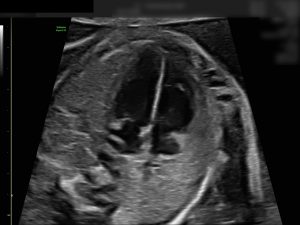

Mit der Feindiagnostik lassen sich alle sichtbaren Organe prüfen, das Herz und die Durchblutung in den Gebärmutterarterien kontrollieren. Ein Ultraschall kann jedoch nie alle körperlichen oder chromosomalen Auffälligkeiten ausschließen.